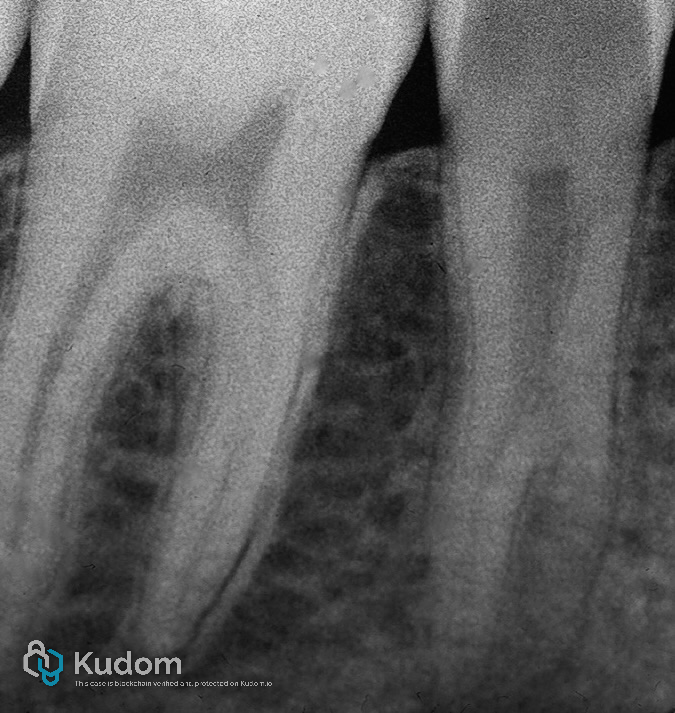

Endodontic Treatment:

Root canal therapy was initiated under rubber dam isolation. Anatomical exploration revealed a complex canal system with three distinct canals, including one with a C-shaped morphology. Thorough cleaning, shaping, and obturation were performed using standard endodontic protocols tailored to the intricate anatomy.

Fig. 3